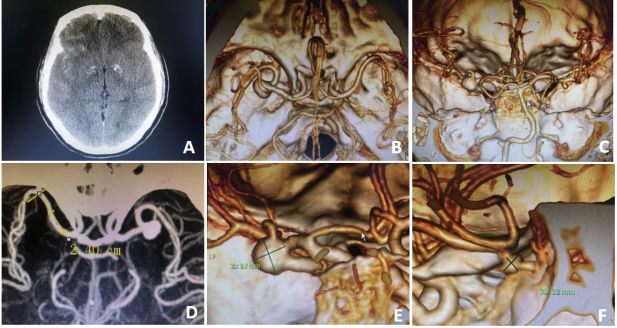

图2 患者手术中动脉瘤夹闭及分支血管保留情况。(A)探查并分离瘤颈周围黏连后充分显露瘤颈,因瘤体张力大,予临时阻断M1段;(B)临时阻断M1段,瘤体张力降低不明显,再临时阻断上干及下干后分离瘤颈 ;(C)蛇牌760及722动脉瘤夹各一枚完全夹闭动脉瘤;(D)荧光造影确认瘤腔内无荧光显影,各分支血管显影满意,并剪开瘤体验证瘤颈完全夹闭。(E)额下分离,牵开眶回内侧部,充分解剖对侧外侧裂后显露M1段,长约24mm;(F)瘤颈被蝶骨嵴遮挡无法显露,使用超声骨刀磨除部分蝶骨嵴;(G)磨除蝶骨嵴后显露动脉瘤瘤颈,约4mm;(H)使用一枚蛇牌740动脉瘤夹成功夹闭对侧M1段动脉瘤。

取左侧标准翼点手术入路,仰卧位,头向右侧旋转30°,轻微后仰。

切口起自耳屏前1cm平颧弓,沿发际弧形切口到达中线,铣刀开颅形成一大小约4cm×6cm大小骨瓣,充分磨平蝶骨嵴,硬脑膜张力不高,显微镜下剪开硬膜,Paine点穿刺侧脑室释放脑脊液,充分分离侧裂,于分叉部探查见动脉瘤,大小约10*8mm,瘤颈宽约9mm,朝向外上方,瘤体张力高,予临时阻断M1段,张力仍较高(图2A),故继续临时阻断上干及下干(图2B)后分离周围黏连并充分暴露动脉瘤颈,使用一枚蛇牌760夹尽量平行M2平面并垂直M1夹闭大部分瘤颈,探查上干下方少许残留使用另一枚蛇牌722迷你夹夹闭(图2C),荧光造影确认瘤腔内无荧光显影,载瘤血管及分支血管荧光显影良好(图2D)。

不断调整脑压板牵拉方向,充分解剖视交叉池及对侧外侧裂,牵开对侧眶回内侧部,探查对侧大脑中动脉M1段(图2E),对侧M1段长约2.4cm,动脉瘤显露困难,根据术前CTA提示,动脉瘤位于蝶骨嵴下方,瘤颈被蝶骨嵴遮挡无法显露,予切开蝶骨嵴硬膜后,超声骨刀磨除部分蝶骨嵴骨质后显露瘤颈(图2F),瘤颈宽约4mm(图2G),使用一枚蛇牌740夹成功夹闭瘤颈(图2H)。术区彻底止血,逐层关闭切口,结束手术。

患者术后意识清楚,言语正常,四肢肌力肌张力均正常,神经系统查体无阳性体征。头皮切口7天拆线,甲级愈合,术后10天顺利出院。 术后复查头颅CT术区未见出血或梗塞灶。CTA提示双侧动脉瘤瘤颈均完全夹闭,未见残留。载瘤动脉及各分支血管均通畅。(图3)

图3:患者术后术后复查头颅CT术区未见出血或梗塞灶。CTA提示双侧动脉瘤瘤颈均完全夹闭,未见残留。载瘤动脉及各分支血管均通畅。